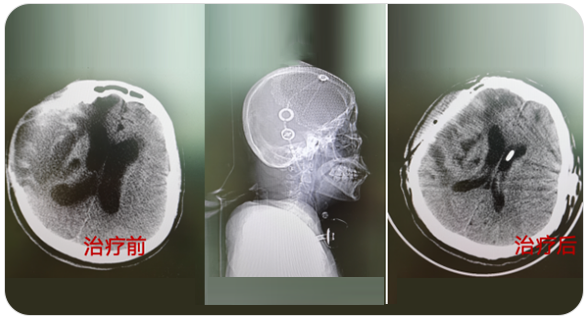

神經(jīng)創(chuàng)傷與重癥中心主要是針對神經(jīng)系統(tǒng)疾病的急危重癥患者進行全面地救治,涉及顱腦創(chuàng)傷以及出血的各種常規(guī)開顱、顯微/內(nèi)鏡下顱底修復與重建、復合手術(shù)、復雜的腦積水和顱面骨缺損修復成形手術(shù)、綜合治療神經(jīng)系統(tǒng)感染等。

擅長腦血管病(出血與缺血)的神經(jīng)介入與微創(chuàng)手術(shù),能熟練開展腦外傷、重度顱腦損傷的救治工作。